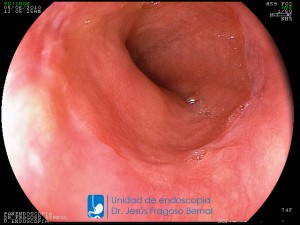

La Unidad de Endoscopía fue creada en 2002 por el Dr. Jesús Fragoso Bernal, es pionera en el estado por la utilización de la tecnología más avanzada, que nos permite ofrecer servicios integrales de diagnóstico y tratamiento para las enfermedades del aparato digestivo.

El profesionalismo de nuestro personal, altamente especializado, se distingue por la calidad y calidez de nuestros servicios con el objetivo de brindar una atención de excelencia en el ambiente más confortable para comodidad y seguridad de nuestros pacientes.

"La Unidad de Endoscopía se ha caracterizado por un progreso continuo desde su inicio marcando la pauta en los procedimientos endoscópicos en el estado de Tlaxcala y estando siempre a la vanguardia tecnológica."

Dr. Jesús Fragoso Bernal